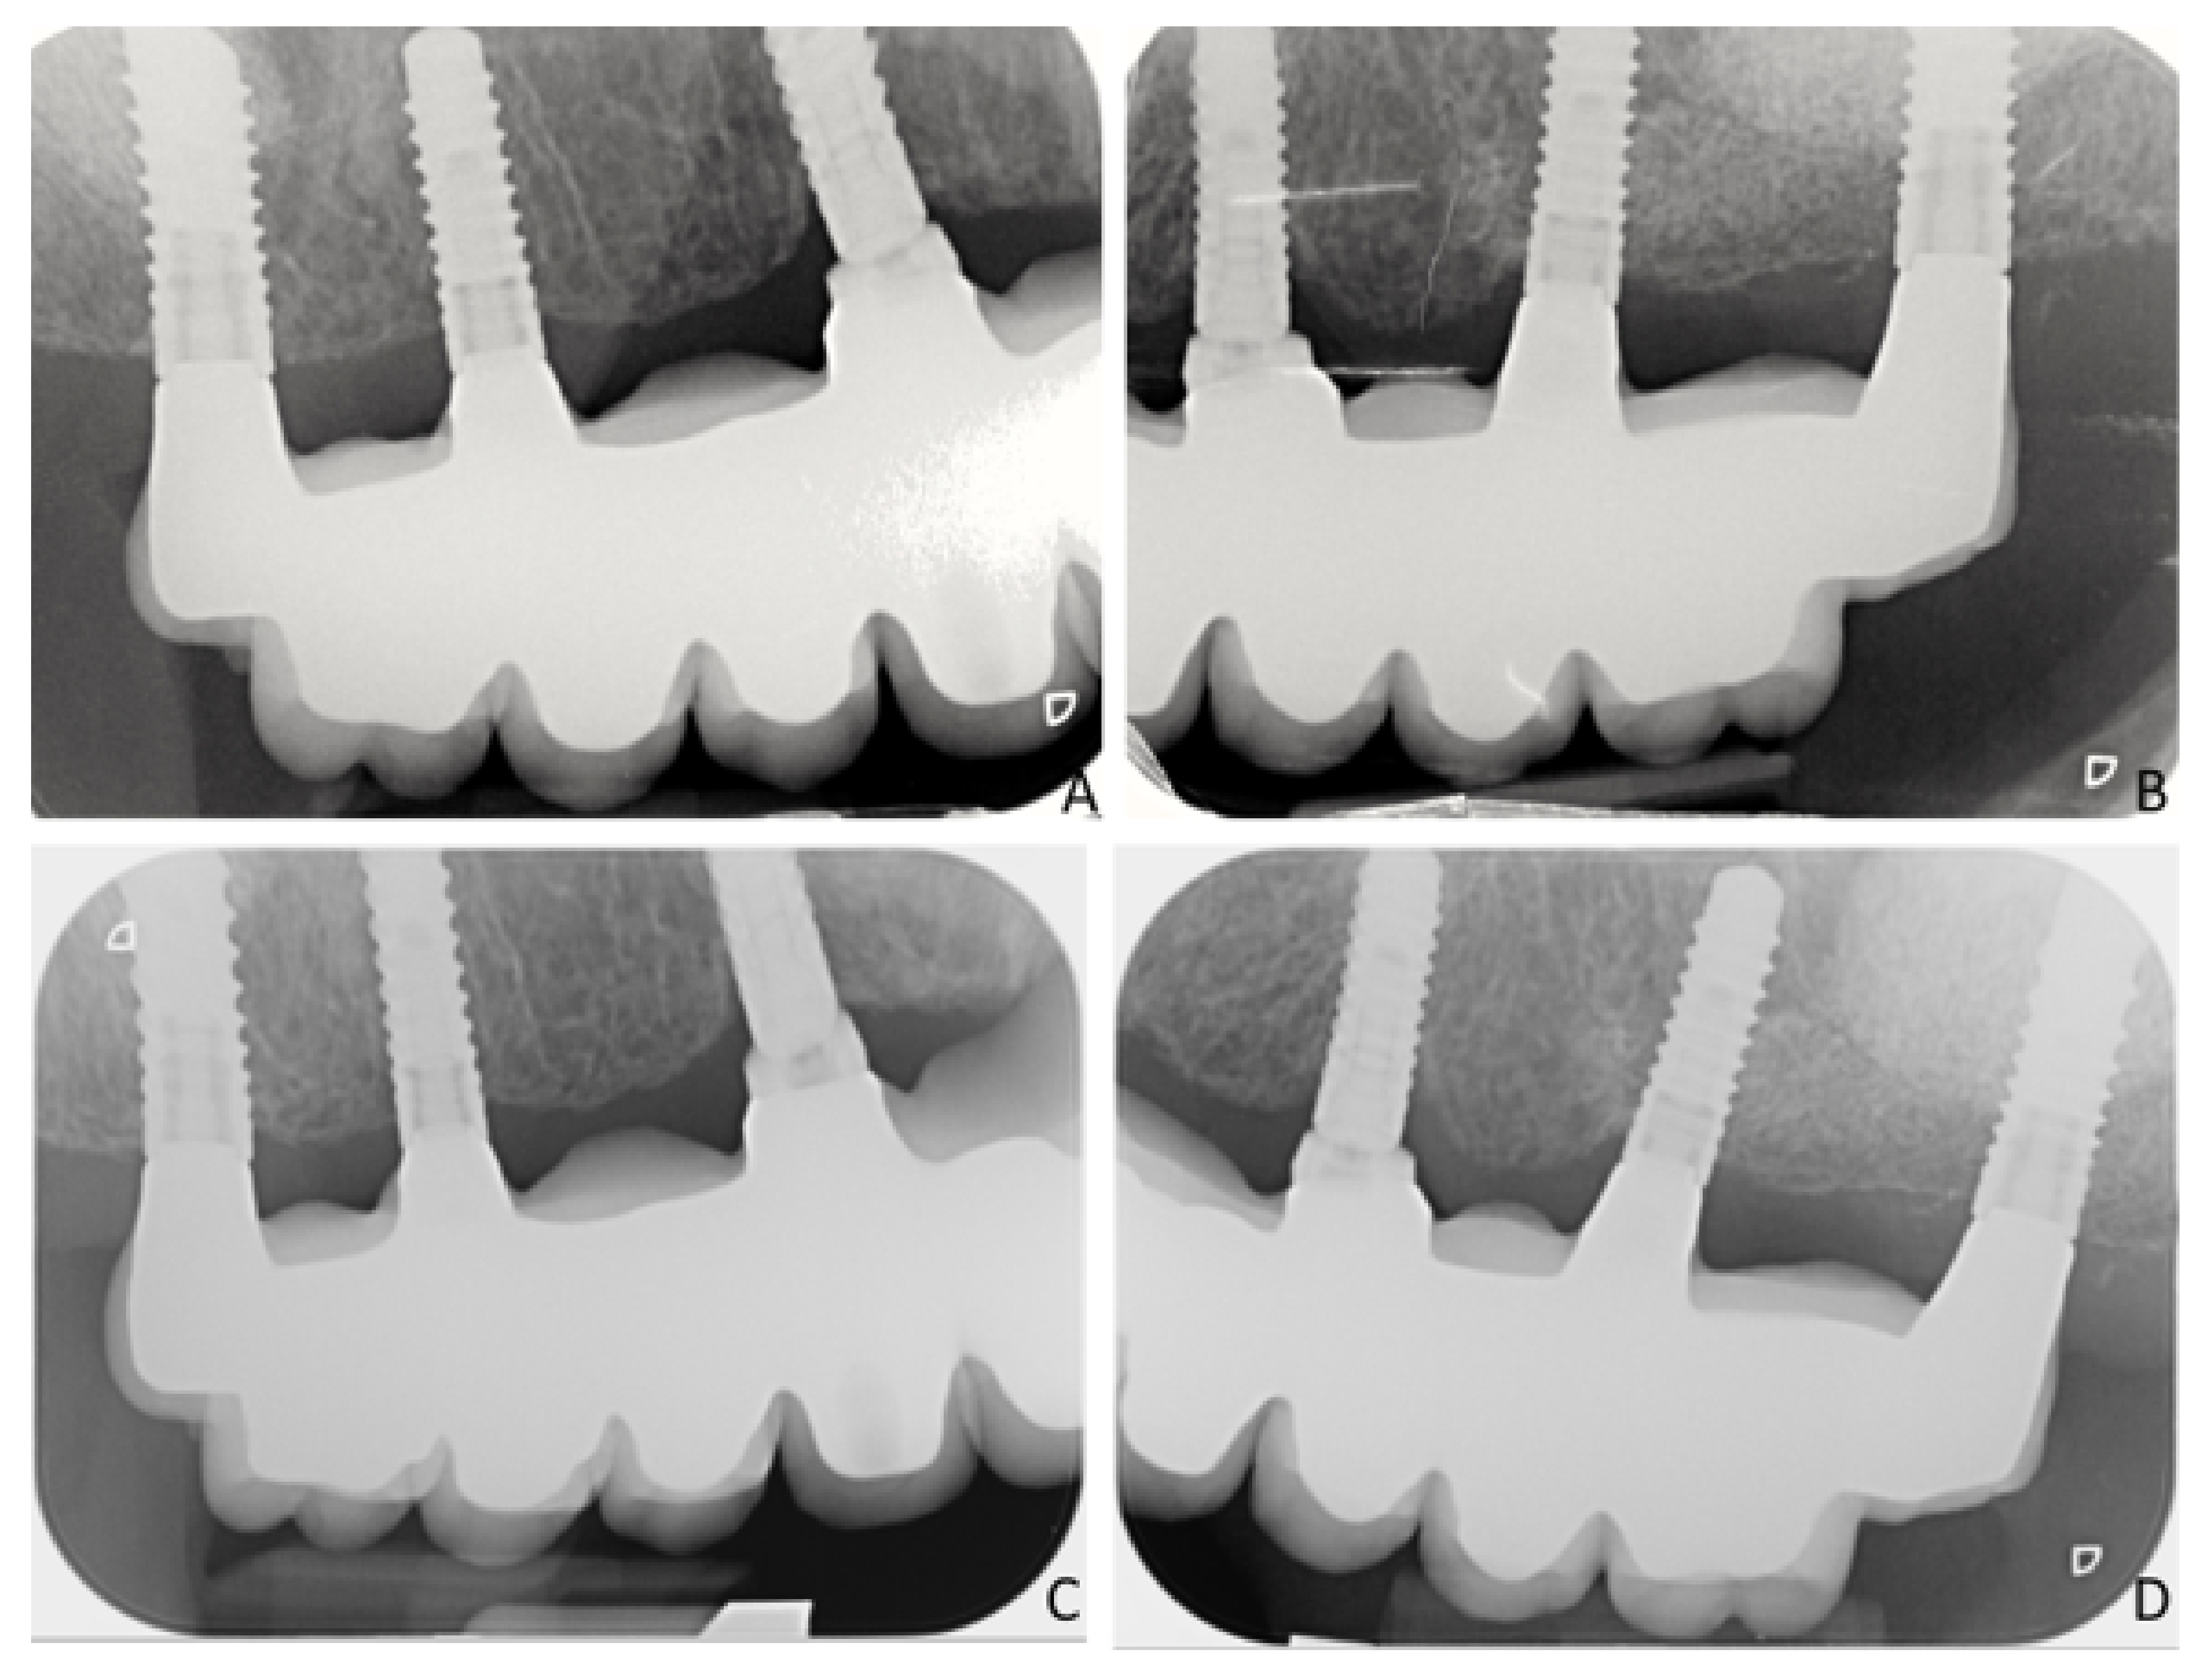

Two-Year Follow-Up of 4-mm-Long Implants Used as Distal Support of Full-Arch FDPs Compared to 10-mm Implants Installed after Sinus Floor Elevation. A Randomized Clinical Trial

2.11. Radiographic Measurements

| MBL Short | MBL Control | Progressive Changes Short | Progressive Changes Control | |

|---|---|---|---|---|

| Prosthesis delivering (BL) | 0.17 ± 0.41 | 0.28 ± 0.21 | NA | NA |

| 6 months | 0.18 ± 0.34 | 0.49 ± 0.44 | −0.01 ± 0.11 | −0.21 ± 0.33 |

| 12 months | 0.21 ± 0.35 | 0.58 ± 0.44 | −0.04 ± 0.13 | −0.30 ± 0.32 |

| 18 months | 0.34 ± 0.35 | 0.68 ± 0.51 | −0.17 ± 0.29 | −0.40 ± 0.37 |

| 24 months | 0.44 ± 0.37 | 0.84 ± 0.68 | −0.28 ± 0.37 | −0.54 ± 0.49 |